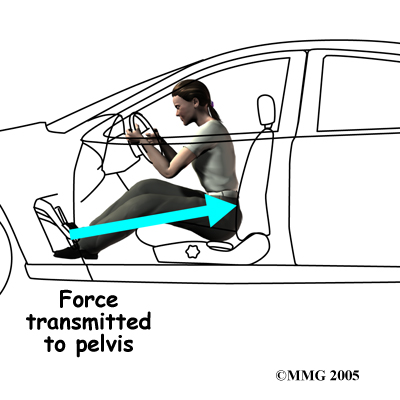

There are many different causes of SI joint pain. As mentioned, pregnancy may be a factor in the development of SI joint problems both at the time of pregnancy, but also later in life. If a person has one leg that is shorter that the other, the abnormal alignment may end up causing SI joint pain and problems. Stiff SI joints may cause pain depending on the activity that one is trying to undertake. An ankylosed SI joint, which is a joint that becomes fused due to disease and therefore doesn’t move at all, may do the same. Traumatic events such as motor vehicle accidents, falls, or jarring events particularly onto one leg or one side of the buttocks can also cause SI joint pain.

One common pattern of injury from a motor vehicle accident occurs when the driver places one foot on the brake before a collision. The impact through the foot on the brake is transmitted to the pelvis causing a twisting motion to one side of the pelvis. This can injure the SI joint on that side resulting in pain. A similar mechanism occurs with a fall onto one buttock or onto one leg, such as stepping into a deep hole or unknowingly off of a large curb. Again, the force through one side of the body, which causes a relative twisting motion to the pelvis, can injure the ligaments around the SI joint.